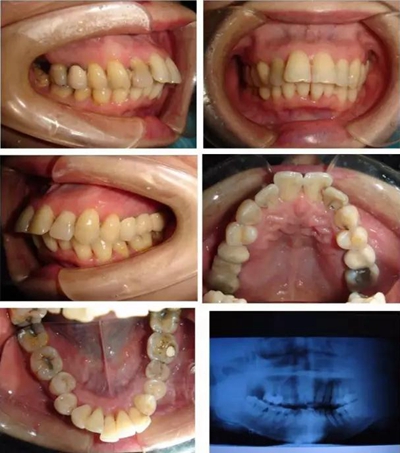

▲ 圖 輕中度患者骨性前突患者

來自鞍山市鐵東區(qū)口腔醫(yī)院劉啟明醫(yī)生,采用微種植體支抗矯治成人輕中度骨性前突的臨床應(yīng)用,并取得良好成績,其論文刊登《中國美容醫(yī)學(xué)》2017年5期。